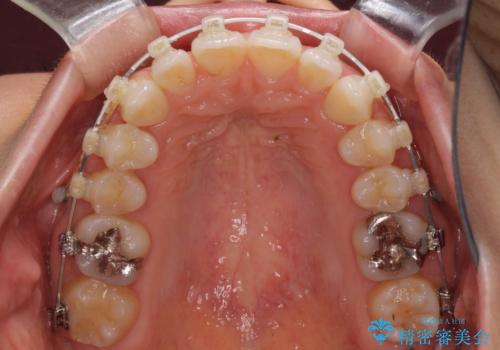

咬合力が強いため、アンカースクリューを使用し、ワイヤー装置にて矯正治療を行うこととしました。

上顎歯列を下顎に対して4mmほど移動させる必要があったため、治療は長期化することが予想されましたが、患者様にはこちらの期待以上にゴムかけなどに協力いただき、補綴治療も含めて2年強で終えることができました。